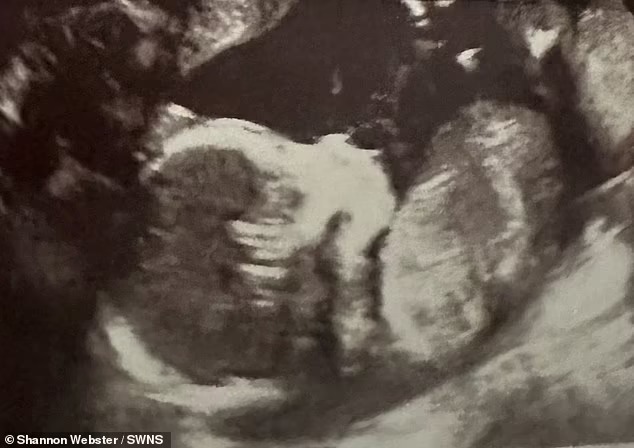

وفي تطور آخر، كشفت عمليات المسح في أثناء حملها التالي بطفلها الأصغر أنها كانت تحمله في رحمها الأيمن، على عكس طفلها الأول الذي حملته في رحمها الأيسر، وقالت السيدة ويبستر إن تشخيصها جعل تجاربها مع مشاكل الدورة الشهرية الماضية أكثر منطقية.

وأضافت شانون ويبستر، بعد أن أجهضت في عام 2016، تم الكشف عن حالتي خلال الموجات فوق الصوتية، وتبين أن لدي رحمين، وهذا نادر جدًا، وأكد فحص آخر بالرنين المغناطيسي في نفس العام أن لدي رحمًا مزدوجًا، ولكن الأطباء لم يتمكنوا من التحقيق في وقت لاحق من ذلك العام عندما اكتشفت أني حامل مرة أخرى.